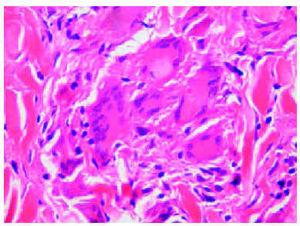

Se tomaron varias biopsias de diferentes lesiones cutáneas del tronco y las extremidades, que mostraron un cuadro similar en todas ellas de granulomas en la dermias superior y media (fig. 3). La extensión de los granulomas varió según las piezas. Los granulomas eran principalmente pequeños y bien definidos, y contenían células epitelioides y células gigantes multinucleadas. Había pocos linfocitos, de aspecto normal. Algunos granulomas estaban formados principalmente por células gigantes con numerosos núcleos (fig. 4), y algunas células gigantes contenían cuerpos asteroides. La epidermis estaba adelgazada y aplanada, y no había inflamación granulomatosa en la zona subepidérmica ni epidermotropismo. Se observaban muy pocas fibras elásticas, así como fagocitosis de las fibras elásticas por las células gigantes. No se observó fagocitosis de linfocitos.

Fig. 3.--Biopsia del muslo que no muestra todavía signos de cutis laxa. Se aprecian granulomas sarcoides en la dermis media con células epitelioides, células gigantes y un rociado de linfocitos. (Hematoxilina-eosina, x25.)

Fig. 4.--Detalle de un granuloma con numerosas células gigantes multinucleadas. (Hematoxilina-eosina, x200.)